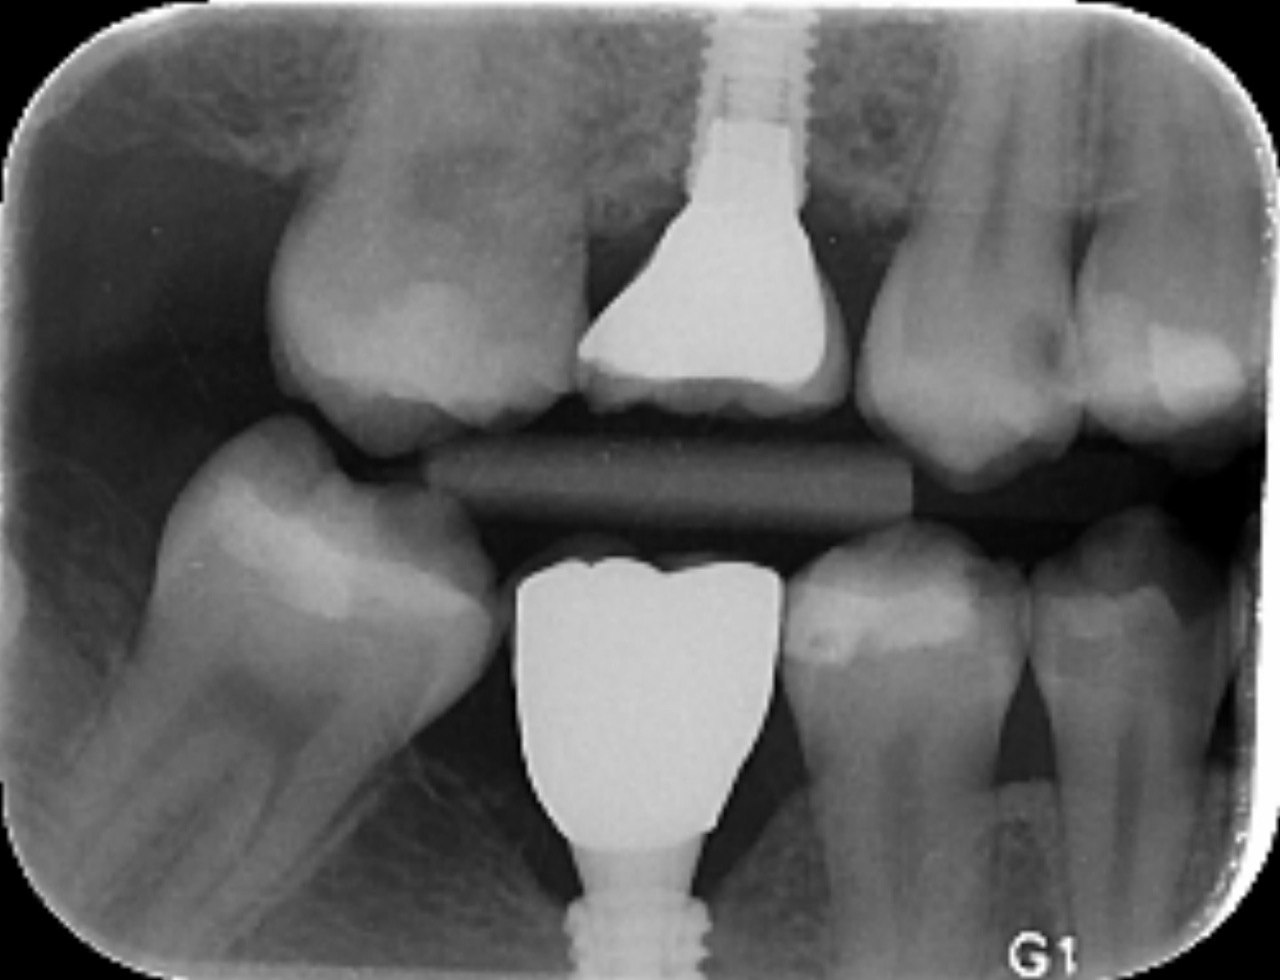

1. What surface require restoration?